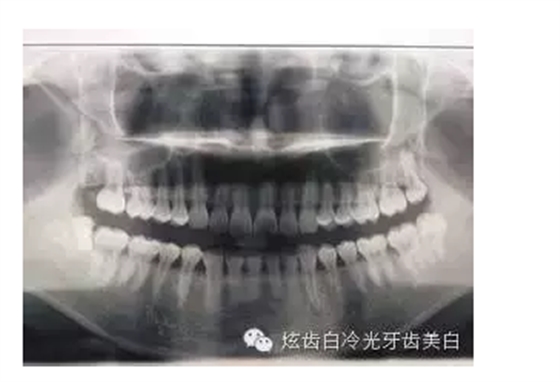

6、X光片檢查:顯示齲壞程度,牙根,牙槽骨的情況。